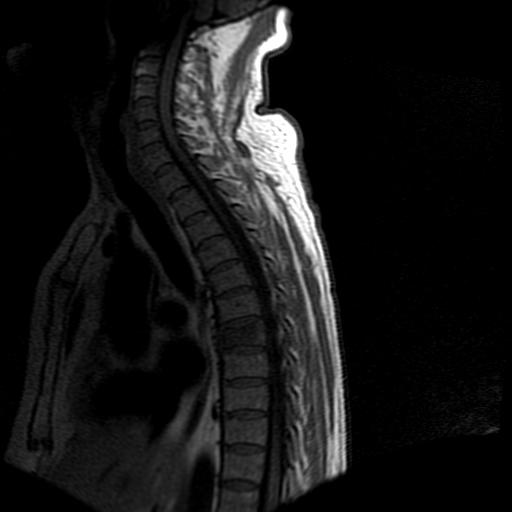

标题: MRI0985:胸椎.68岁男性,胸部疼痛,

68岁男性,胸部疼痛,不适。

t7椎体前1/3信号略减低,椎体上下面凹陷,相应脊髓几周边软组织信号未见改变。考虑:椎体退变。

胸7椎体楔状变形及信号异常,附件未见明显异常信号.椎间隙正常.未见软组织块影.考虑骨质疏松所致压缩性骨折可能大.

胸7椎体楔状变形及信号异常[t1t2 均为低信号],附件未见明显异常信号.椎间隙正常.未见软组织块影.考虑陈旧性压缩性骨折伴退变。